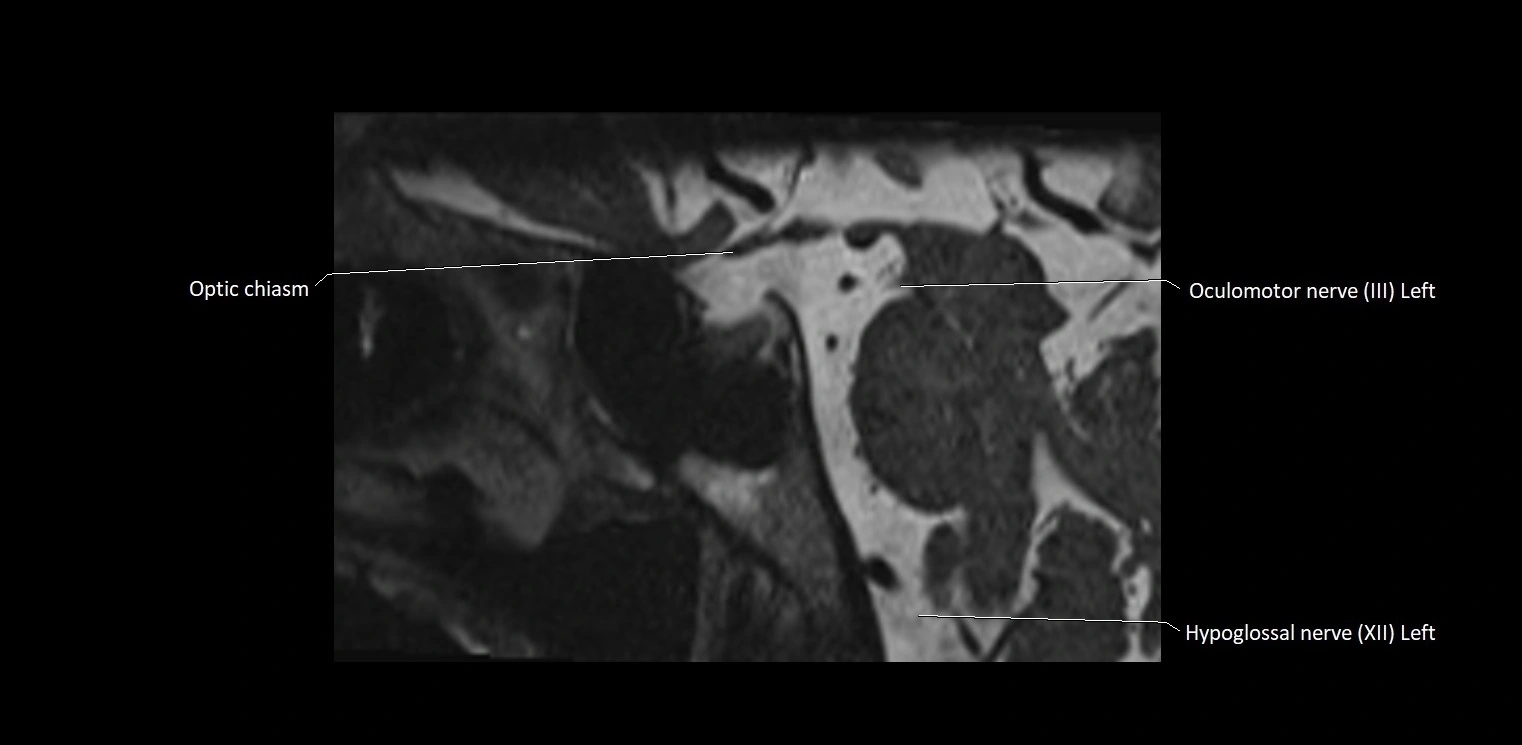

MRI Appearance

• The abducens nerve is a small, thin, linear structure

• Best visualized on high-resolution T2-weighted 3D MRI sequences (e.g., FIESTA or CISS)

• Seen as a hypointense (dark) line running from the brainstem at the pontomedullary junction, traversing the prepontine cistern, and entering Dorello’s canal under the petrosphenoidal ligament, then into the cavernous sinus, and finally the orbit

• May be challenging to visualize in standard MRI due to its small size

• Pathology may be inferred by absence, displacement, or enhancement of the nerve